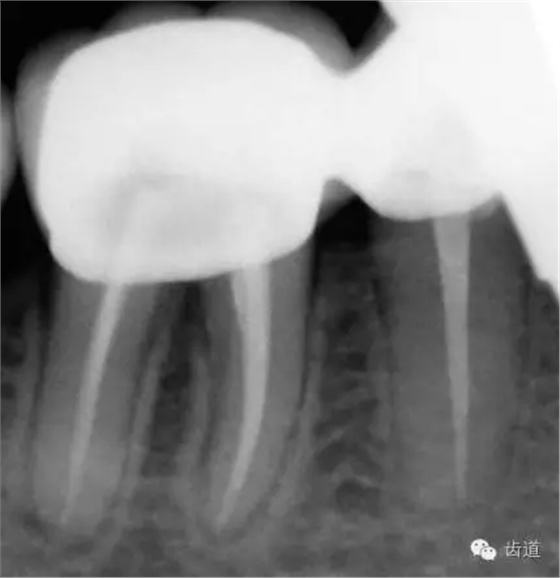

6、45,46,47牙片

45,46去除原充填物和齲壞,揭全髓室頂,46探及近頰近舌遠中三根管,45單根管,超聲輔助清理髓腔及根管,去除根管內(nèi)充填物,根管下段細小堵塞欠通暢,8號/10號C銼疏通根管,pathfile+protaper鎳鈦根管預(yù)備,熱牙膠根管充填。